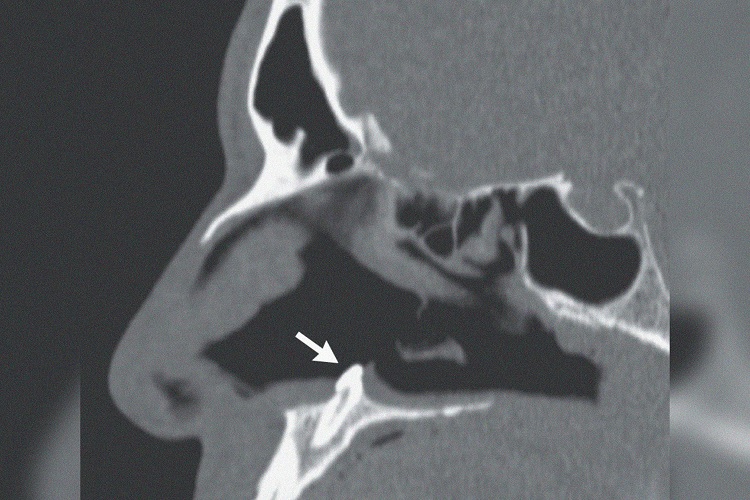

Исследование выявило искривленную перегородку и «твердую белую массу», находящуюся в глубине ноздри. Компьютерная томография подтвердила, что причиной затруднения дыхания оказался зуб. По словам медиков, появление зуба в нетипичном месте — крайне редкое заболевание, которое встречается примерно у 0,1 процента населения. Гораздо чаще зубы прорастают неправильно — например, в перевернутом состоянии — и выпадают сами.

В результате операции медики извлекли из носовой полости зуб около 14 миллиметров в длину и 10 миллиметров в ширину. «Через три месяца после операции у пациента исчезли симптомы заложенности носа», — подытожили врачи.